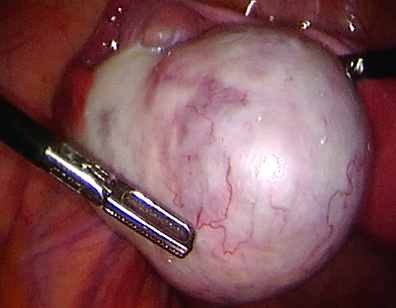

The tube is being opened to reveal the pregnancy